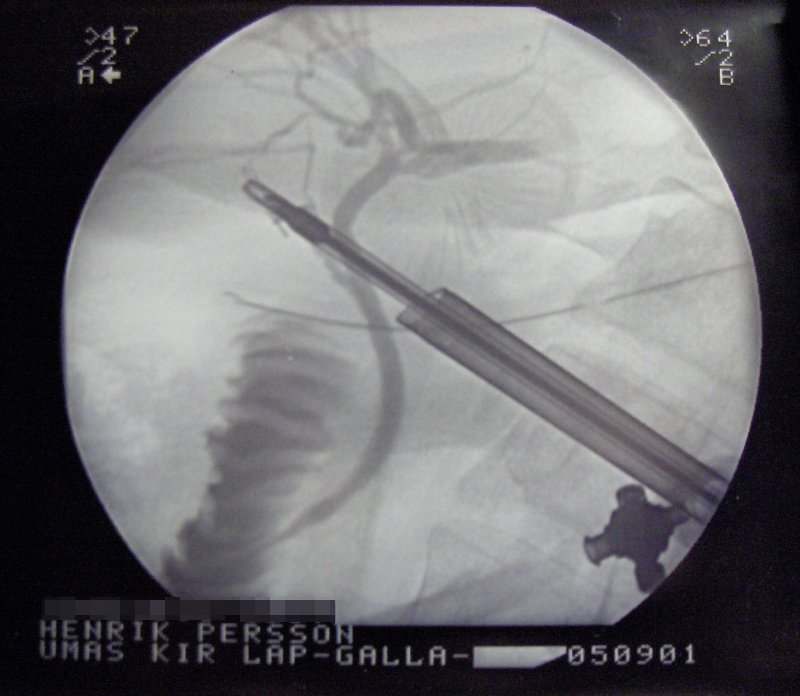

현재는 복부에 5mm에서 10mm의 작은 구멍을 3~4군데 뚫어 복강경으로 환자의 체내를 확인하면서 시행하는 복강경 담낭 절제술이 주류를 이루고 있다. 개복 수술에 비해 일상생활로의 복귀가 빠르고, 환자의 부담도 적다는 장점이 있다. 담낭염의 진행 정도나 기타 병상에 따라 복강경 수술이 불가능한 상황도 있다. 사전 검사에서 복강경 담낭 절제술을 시행할 수 있다고 진단받더라도 수술을 시작하고 처음 밝혀지는 병상이 있기 때문에 5%의 확률로 수술 중 개복 수술로 변경될 가능성이 있다.

5. 2. 담낭 절제술

대부분의 급성 쓸개염 환자에게 선택되는 치료법은 복강경 담낭 절제술을 통한 담낭의 외과적 제거이다.[32] 복강경 담낭 절제술은 복부 전체의 여러 지점에 위치한 몇 개의 작은 절개를 사용하여 수행된다. 여러 연구에서 개복 담낭 절제술(늑골 아래 오른쪽 상복부에 큰 절개를 사용하는 경우)에 비해 복강경 담낭 절제술의 우수성이 입증되었다. 복강경 수술을 받는 사람들은 수술 후 절개 부위 통증이 적고, 장기적인 합병증과 수술 후 장애가 적다고 보고한다.[33][34] 또한, 복강경 수술은 수술 부위 감염률이 낮다.[35]

현재는 복부에 5mm에서 10mm의 작은 구멍을 3~4군데 뚫어 복강경으로 환자의 체내를 확인하면서 시행하는 복강경 담낭 절제술이 주류를 이루고 있다. 개복 수술에 비해 일상생활로의 복귀가 빠르고, 환자의 부담도 적다는 장점이 있다.

최근에는 복강경을 이용한 담낭 절제술이 주류를 이루고 있다.[45] 복강경 담낭 절제술은 복부에 5mm에서 10mm의 작은 구멍을 3~4군데 뚫어 시행하며, 개복 수술에 비해 회복이 빠르고 환자의 부담이 적다는 장점이 있다. 그러나 담낭염 진행 정도나 기타 병상에 따라 복강경 수술이 불가능할 수 있으며, 수술 중 개복 수술로 변경될 가능성도 5% 정도 존재한다.